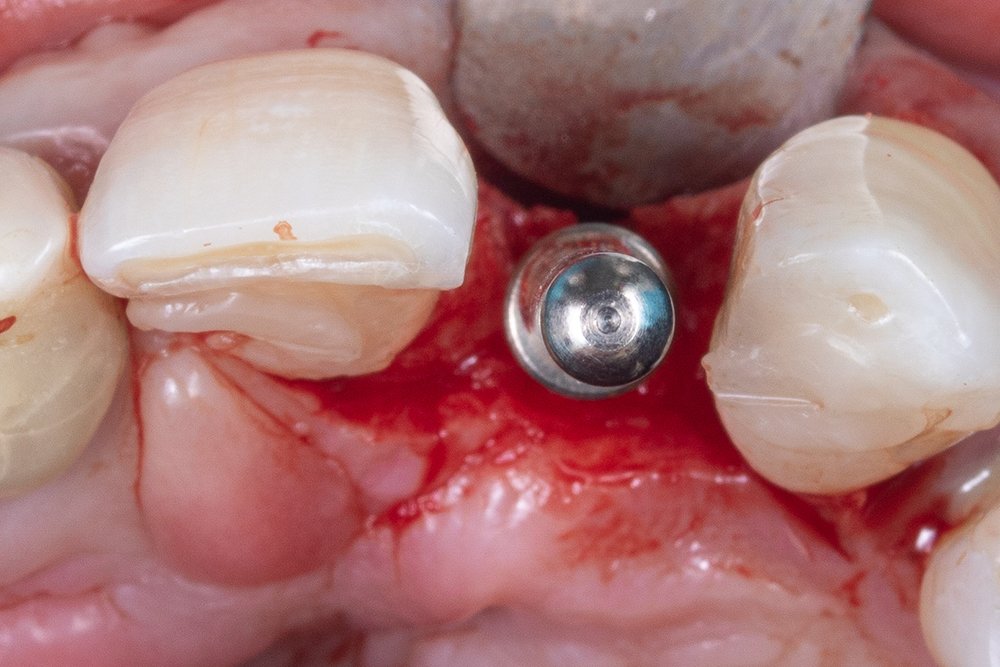

Ao final da instalação do implante, é importante mensurar a distância do implante intraósseo, devendo ficar de 2 a 3 mm, considerando a mucosa peri-implantar.

Para a escolha do munhão, componente responsável por receber a peça protética, foi utilizado o pilar reto da linha IDEALE (Implacil De Bortoli).

Neste caso, foi realizado um provisório imediato, considerando sua importância para a cicatrização tecidual e definição do perfil de emergência.